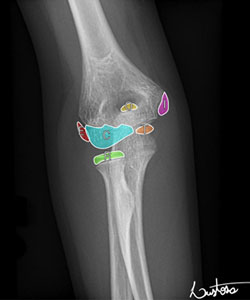

The elbow has six ossification centers, and the medial epicondyle is the last one to fuse which makes this injury common in adolescents when the ossification center is weakest. This ossification center does not contribute to longitudinal growth so injuries to the medial epicondyle do not cause a significant length discrepancy between the two arms; however, it can cause a painful nonunion if it does not heal, especially in throwing athletes. Figure 2 shows the 6 ossification centers in the elbow with “I” indicating the medial epicondyle. The blood supply comes from branches of the inferior ulnar collateral artery and branches of the superior and inferior ulnar collateral artery.

Image Courtesy - https://radiopaedia.org/articles/ossification-centres-of-the-elbow?lang=us

Figure 2